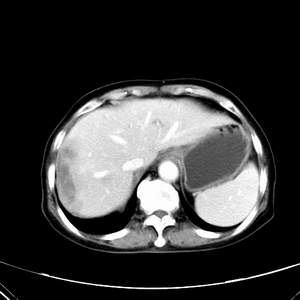

患者,女性,77岁,右上腹胀痛月余。afp正常。ca125升高。即往无肝炎病史。

肝右叶病灶是胆管细胞癌吗?门静脉右支癌栓形成?右侧肾上腺有问题吗?

快进快出符合肝癌表现

最后5幅图片是延时7分钟的。门静脉右前支内有充缺吗?如有,肝血管瘤不好解释。

渐进性强化,中间见沙砾样钙化,首先考虑血管瘤

病灶渐进性向心性强化,延时病灶中心见条片状高密度影,局部见肝包膜回缩征,结合病人无肝炎病史,考虑肝右叶胆管细胞癌,门脉右支癌栓形成。